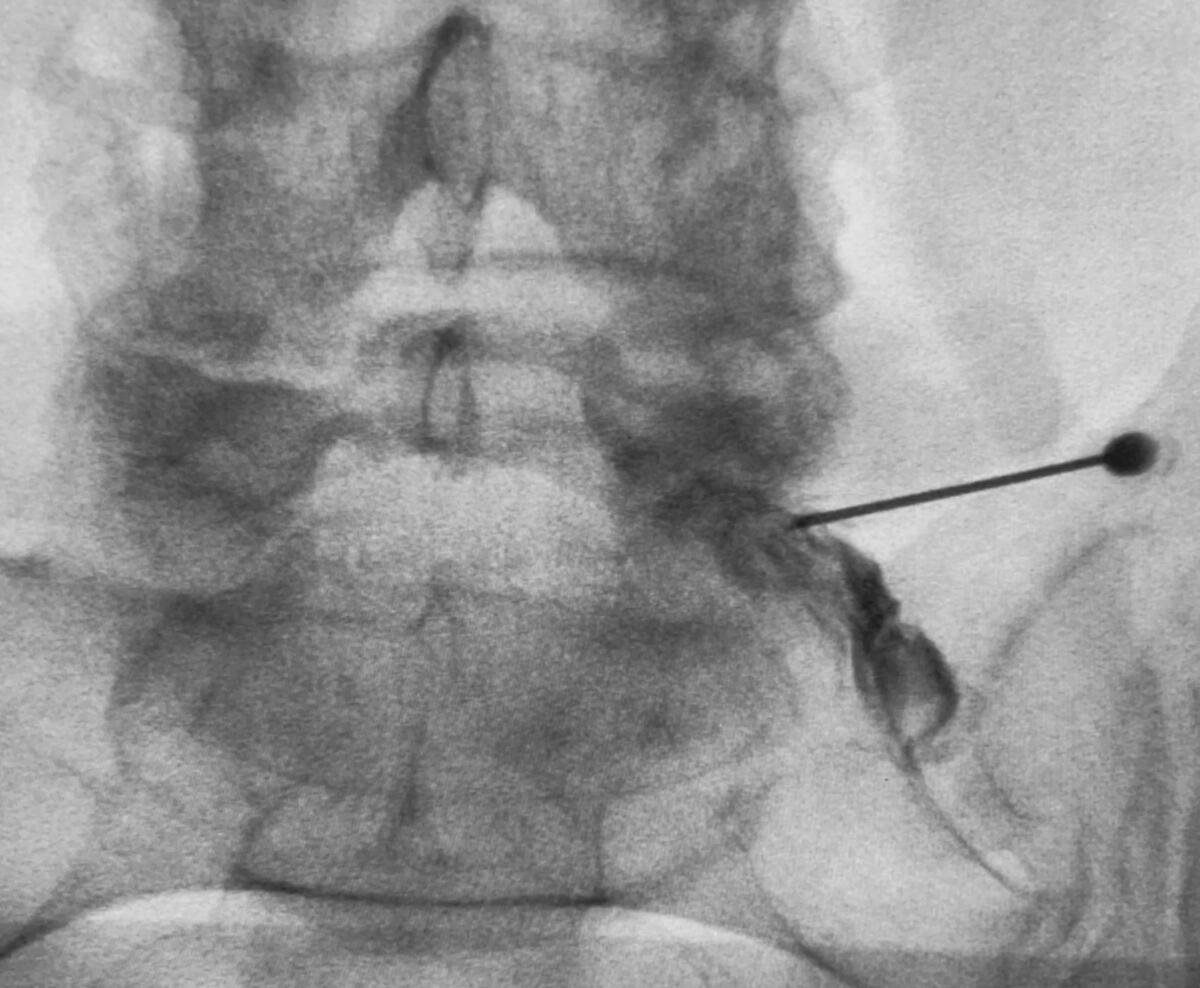

Transforaminal epidural nerve root injection

Image gallery

Some examples of our work

Transforaminal epidural for spinal nerve root pain